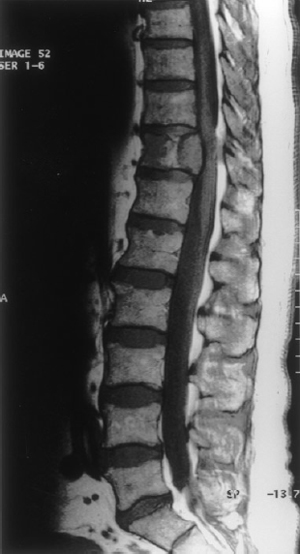

A 62 year old male presented with back pain of several weeks duration. Initial CT of the lumbosacral spine was normal.Examination of the lower limbs revealed mild hyperreflexia, otherwise a normal examination. An MRI scan of the spine was performed which revealed a lesion in the posterior aspect of the T11 vertebral body with extension into the right pedicle (see Figs 1 and 2). Thorough investigation revealed a large

lesion in the left kidney and a provisional diagnosis of renal cell metastasis to the T11 vertebra was considered the most likely scenario.

Fig. 1 Tumour in the posterior aspect of T11 vertebral body with dural compression.